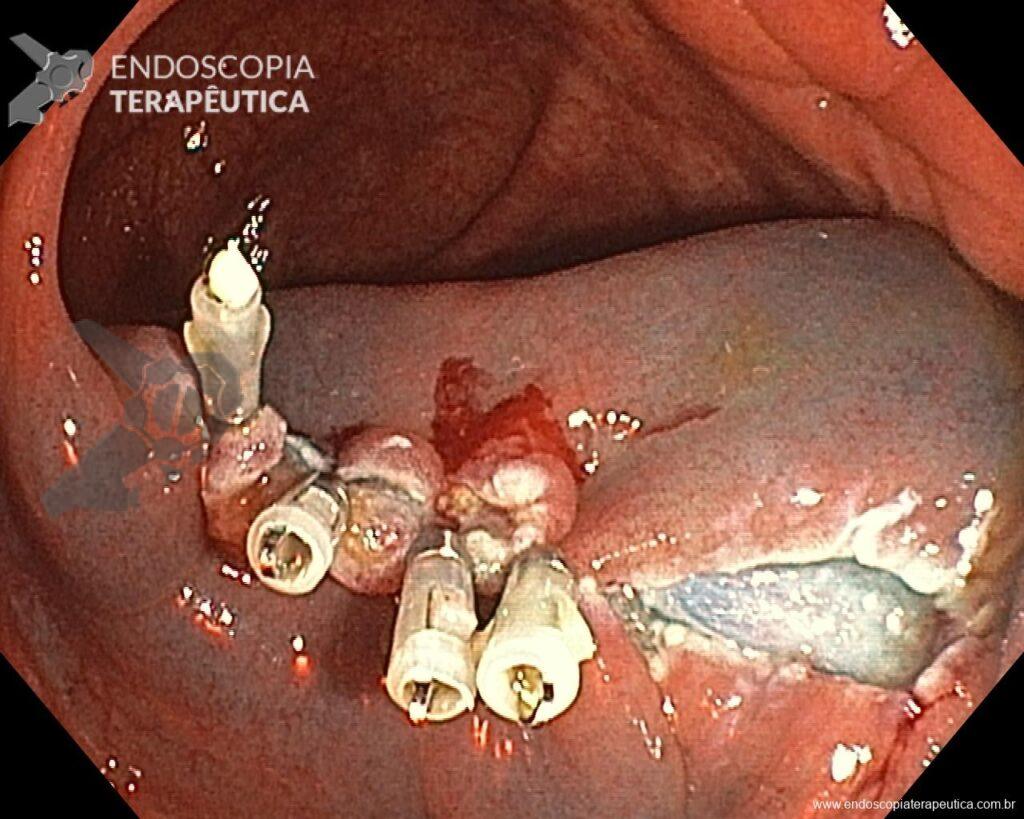

Una vez elegida la técnica de EPMR, tenga en mente que el objetivo debe ser la remoción completa de la lesión con la mayor seguridad posible. Para eso, la estrategia correcta es fundamental: no haga la burbuja submucosa toda de una vez, en vez de eso, haga inyecciones sucesivas seguidas del corte, preferentemente en el sentido proximal-distal; siempre que disponible, dé preferencia a soluciones viscosas, que garanticen una mayor patencia de la burbuja; utilice un asa más pequeña (10-15 mm) para sujetar la ampolla formulada; además de facilitar la operación, reduce el riesgo de perforación al intentar sujetar toda la lesión inadvertidamente.

5. No se preocupe por el sangrado

Si experimenta un sangrado intraoperatorio (SIP), no se preocupe, es solo sangrado. Si bien es cierto que solo la experiencia práctica le dará confianza con el SIP, prepárese para abordarlo sistemáticamente, como lo haría con cualquier otro procedimiento endoscópico. Antes de comenzar el procedimiento, asegúrese de que su sala de endoscopia esté completamente equipada y sea capaz de manejar todo tipo de SIP. Use todo lo que pueda sin preocuparse. Use la bomba de lavado para extraer la sangre del tejido objetivo y limpiar el punto donde necesita intervenir. Si considera que el vaso es pequeño (hasta aproximadamente 2 mm), puede coagularlo inmediatamente con la punta del asa en modo de “coagulación suave”. Por otro lado, si el vaso es mayor de 2 mm, usar unas pinzas de coagulación es una estrategia más efectiva. Mientras espera el accesorio, si usa un tapón en la punta del dispositivo, úselo como un dedo y aplique presión sobre el vaso. Una vez que tenga listo el dispositivo, utilice de nuevo la bomba de agua para limpiar la zona, abra la pinza y sujete el vaso, tirando de él hacia usted (y alejándolo de la pared) antes de la coagulación. Se debe minimizar el uso de coagulación con plasma de argón (APC) durante la REM, al igual que los clips hemostáticos, que deben utilizarse cuando, tras haberlo intentado todo, el sangrado persiste.

En vista de lo anterior, para el caso ejemplificado anteriormente, se optó por la resección mediante la técnica EPMR, tanto por el tipo morfológico (LST-G-H) y las características superficiales de la lesión (JNET 2A), como por su ubicación (ciego), que presenta un mayor riesgo de complicaciones.